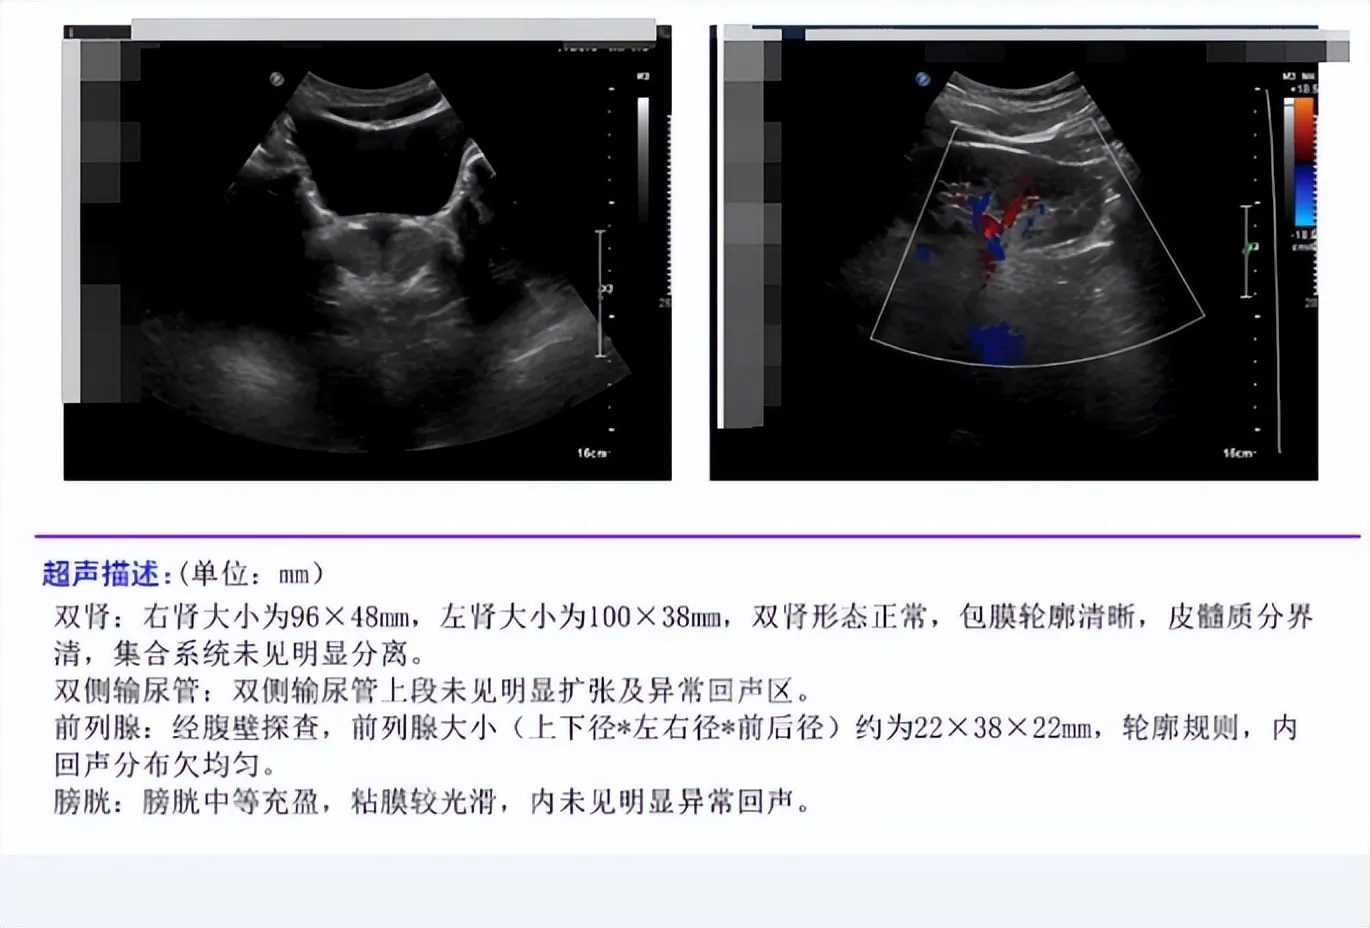

Image